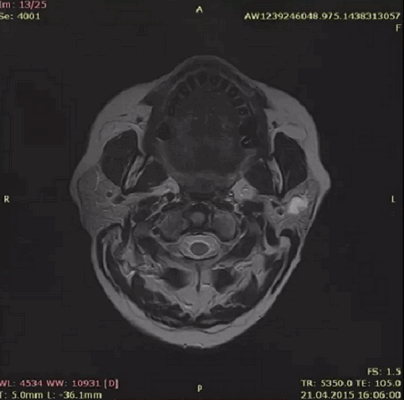

- КТ и МРТ — передают трёхмерное изображение слюнной железы и опухоли, что помогает точно определить её положение и размеры. Также с помощью МРТ можно узнать о строении опухоли, что сделает постановку диагноза более точной [1][2][3][4][5] .

![КТ аденомы слюнной железы [14]](https://probolezny.ru/media/bolezny/adenoma-slyunnoj-zhelezy/kt-adenomy-slyunnoy-zhelezy-14_s.jpg)